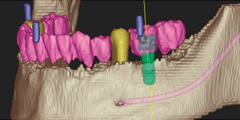

Straumann CARES ガイデッドサージェリー

コンピューターによるシミュレーションソフトウェア“coDiagnostiX”、ガイド製作用装置“gonyX”、そして専用のサージカルガイドにより構成された一貫したシステムにより、手術精度と安全性を劇的に向上させる事を可能にする包括型ソリューション。

サージカルガイド

従来のインプラント埋入手術方法は術者の経験、スキル、感によるのもであった。しかし、Straumann CARES ガイデッドサージェリーで作製されたサージカルガイドを手術時に装着する事により、システマティックなインプラントの埋入深度と埋入角度を実現する事が可能。これにより、術後出血や術後神経麻痺等の合併症を回避でき飛躍的に手術安全性が向上できる。